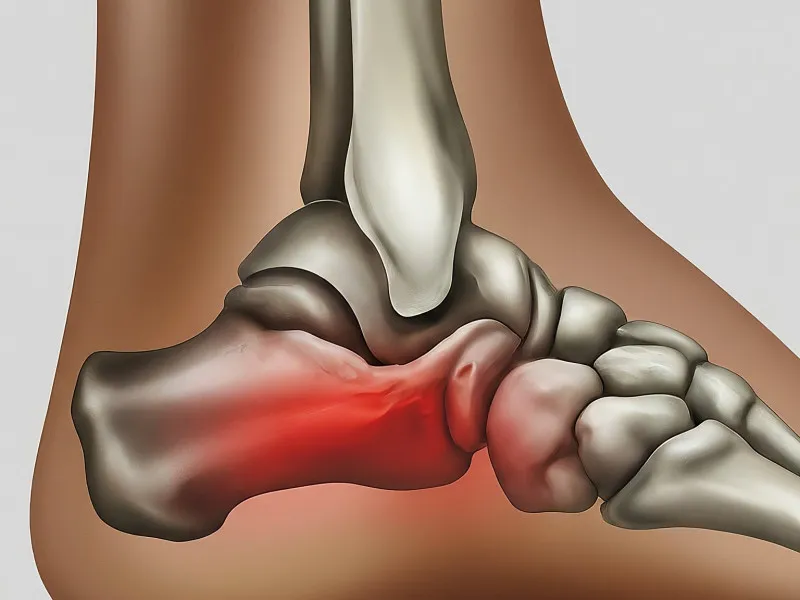

An avulsion fracture occurs when a fragment of bone is torn away by a tendon or ligament from the point of attachment. This type of fracture is commonly seen in athletes and individuals engaging in physical activities that involve a sudden change in motion. Common causes include sports injuries, accidents, and falls. Initial symptoms often involve sudden pain, swelling, and bruising at the site of injury. Diagnosis typically involves physical examination and imaging tests like X-rays to confirm the fracture and evaluate its severity.

Avulsion fractures can affect various areas such as the ankle, hip, and fingers. The severity and treatment depend on the location and extent of the injury. For instance, an avulsion fracture in the ankle may require immobilization, whereas a fracture in the hip might necessitate more intensive intervention. Understanding the mechanism of the injury is crucial for effective diagnosis and treatment.